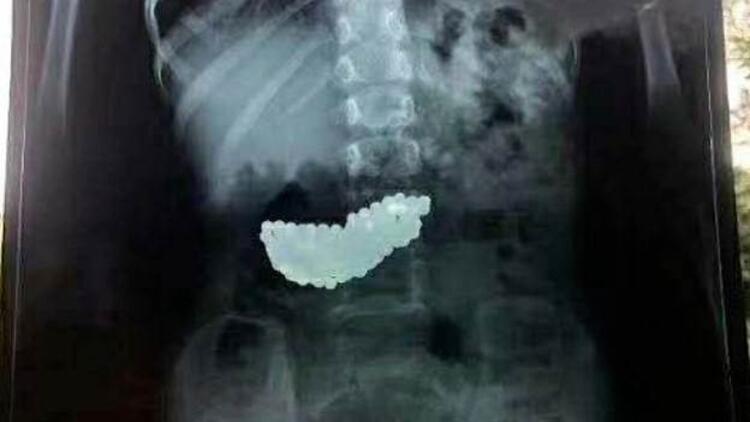

Geçtiğimiz günlerde yine Çin'de yaşanan bir olay da küçük çocuğun midesinden, 190 adet mıknatıslı bilye çıkartıldı. 5 yaşındaki çocuğun, oyun oynarken bilyeleri yuttuğu ve 2 ay boyunca midesinde bu bilyelerle yaşadığı ortaya çıktı.

Çinin Shandong bölgesinde, küçük kızın ailesi, bilyeleri çocuklarının oynarken yuttuğunu ve zamanla doğal yollardan dışarı atıldığını sandıklarını ifade etti. Mıknatıslı olan bilyeler çocuğun midesinde biraraya gelerek büyük bir kitle haline geldi. Bilyeler doğal yollardan çıkmayınca küçük kız 2 ay bu kitleyle yaşadı. Doktorlar röntgenle tespit ettikleri kitleyi ameliyatla çıkardı.